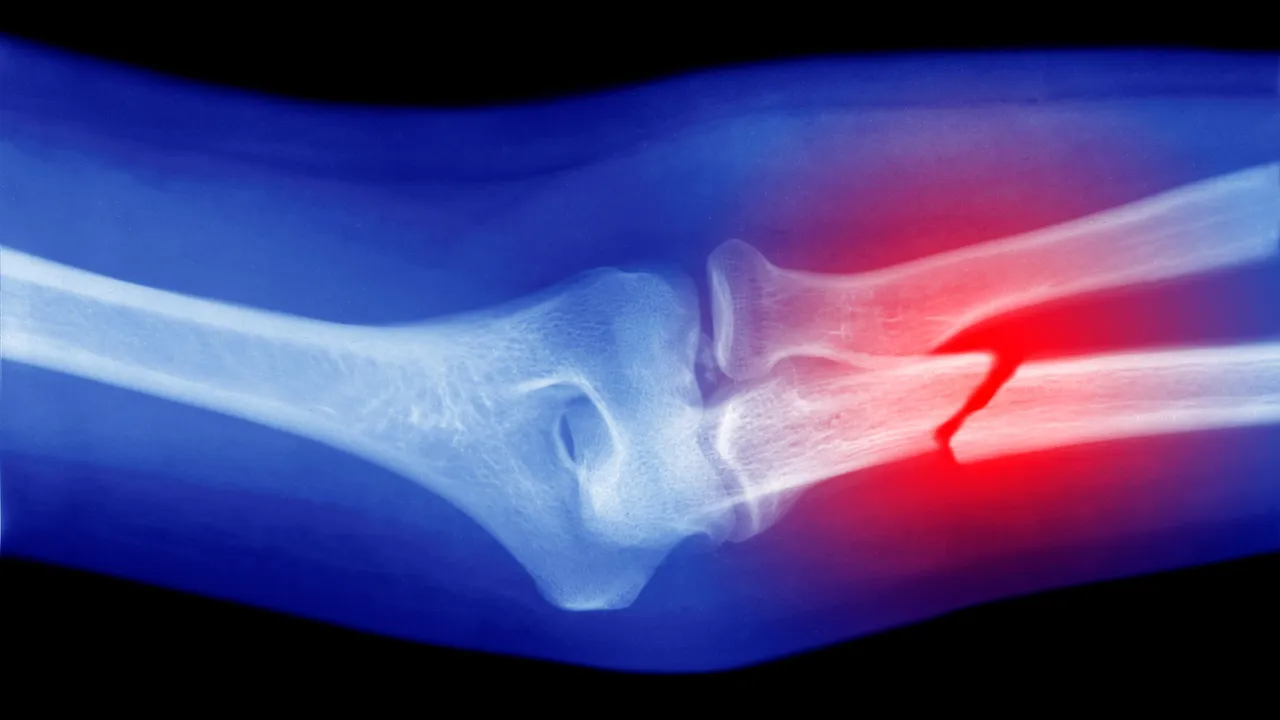

Por su parte, la revisión de estudios in vivo constató que la acumulación de microplásticos en el organismo disminuye el recuento de glóbulos blancos, lo que sugiere alteraciones en la función de la médula ósea. Además, se observó que la aceleración del envejecimiento inducida por los osteoclastos puede asociarse con el deterioro de la microestructura ósea y con displasias, lo que incrementa el riesgo de fragilidad, deformidades e incluso fracturas patológicas.

A pesar de que las enfermedades osteo metabólicas están relativamente bien comprendidas, existe una laguna respecto a la influencia de los microplásticos en su desarrollo. Por ello, uno de nuestros objetivos es generar evidencias que demuestren que estos contaminantes podrían constituir una causa ambiental, y potencialmente controlable, que ayude a explicar, por ejemplo, el aumento proyectado de fracturas óseas”, adelantaron.